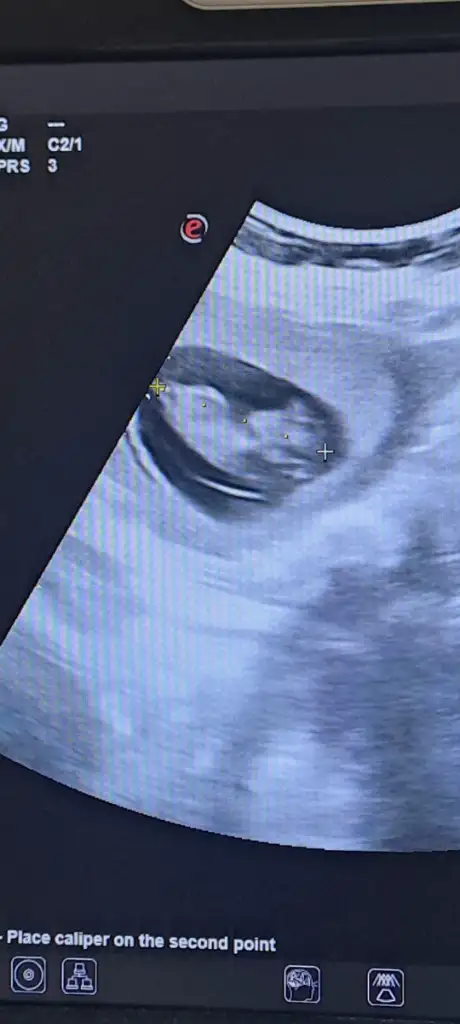

Kıza benziyor, kesenin yuvarlak olması kız fasulye tipi erkek diyorlar ona istinaden13 haftalık anlayan varmı ?

11 haftalık sizce nedir?Erkek sanırım

Bunu kıza benzettim ne zaman öğreneceksiniz11 haftalık sizce nedir?